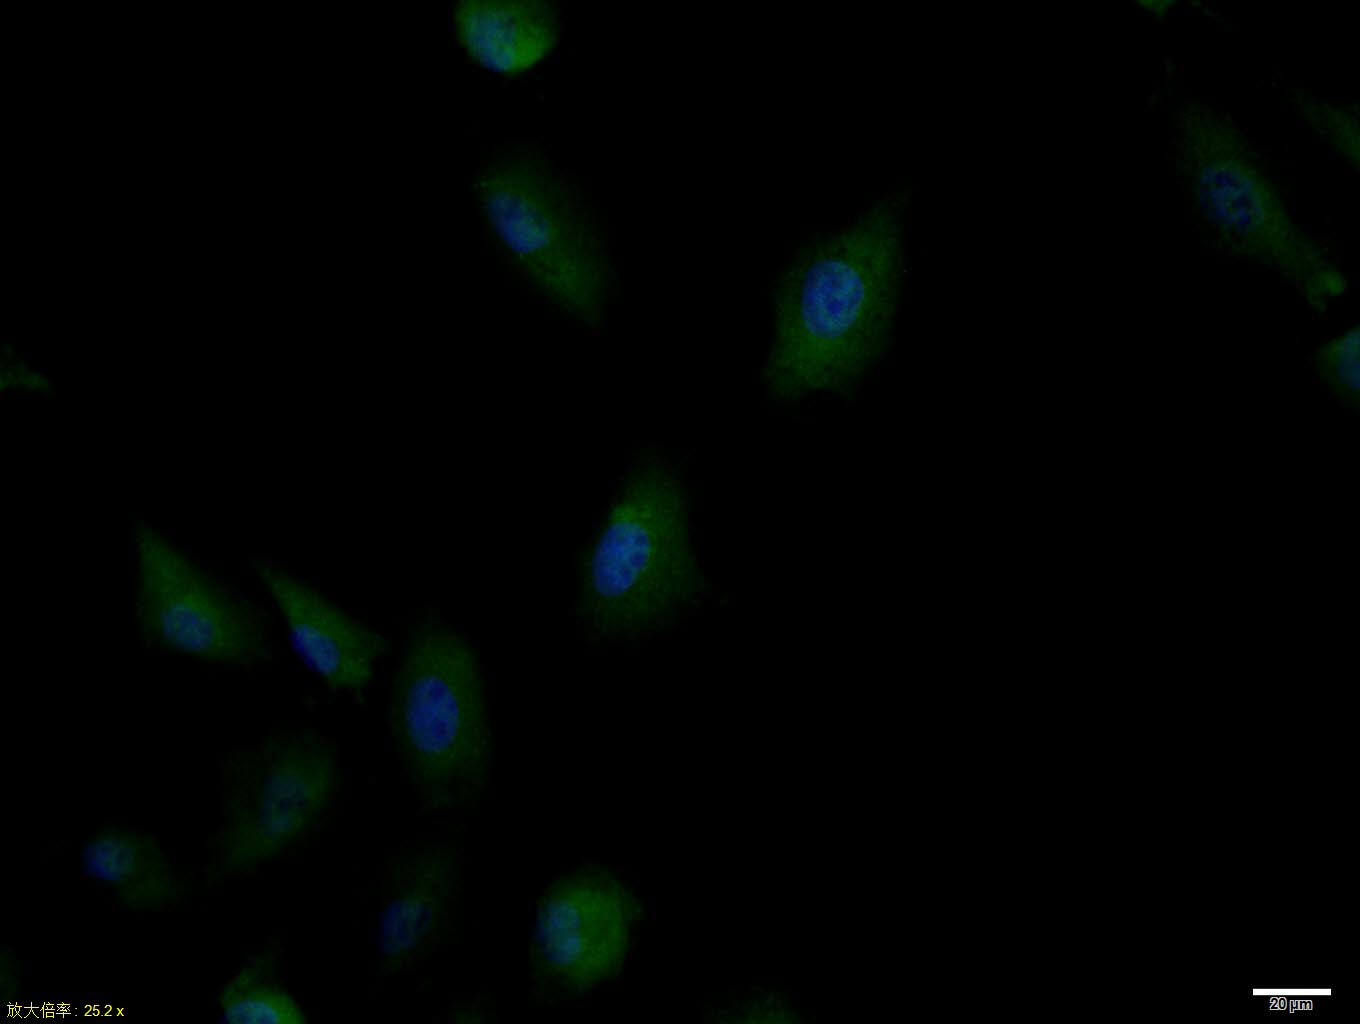

Primary Antibody (green line): Rabbit Anti-phospho-IRS1 (Ser636 + Ser639)antibody (bs-3201R),Dilution: 1μg /10^6 cells;

Isotype Control Antibody (orange line): Rabbit IgG .

Secondary Antibody (white blue line): Goat anti-rabbit IgG-PE,Dilution: 1μg /test.